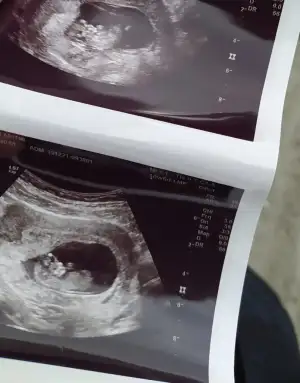

11+0 günlük. cinsiyet tahmininiz var mı acaba?

• WhatsApp Image 2021-12-22 at 11.31.30.webp

WhatsApp Image 2021-12-22 at 11.31.30.webp

44,5 KB · Görüntüleme: 79

• InkedWhatsApp Image 2021-12-22 at 11.25.21_LI.webp

InkedWhatsApp Image 2021-12-22 at 11.25.21_LI.webp

19,4 KB · Görüntüleme: 79